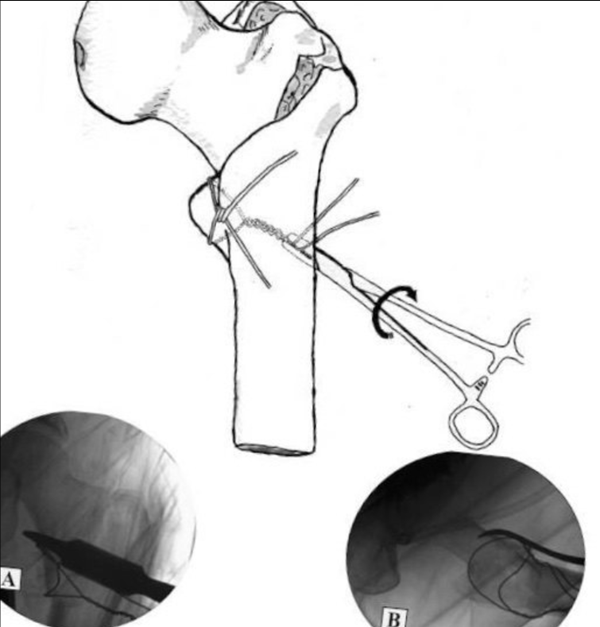

(1)韩国的Kim教授团队继续了Lee教授团队既往的研究,他们将"糖果包钢丝环扎技术”进行改良,先用“糖果包钢丝环扎技术"进行小转子的固定继而使用髓内钉进行转子间骨折的固定。

在股骨大转子部取一长约5-6cm纵形切口,分离小转子周围软组织,以便于实施钢丝捆扎术,先手法整复骨折,对位、对线满意后,在霍夫曼拉钩维持复位下,利用骨折环扎器在小转子近端及远端部分各套入一根钢丝,将股骨前端部分的两根钢丝拧成一股,然后将未拧紧的后边两根钢丝向下拉,使前方已拧紧的结卡在小转子前方(图15)。

图15 糖果包环前方结的打法。A,利用骨折环扎器套入两根钢丝;B,小转子前方两根钢丝拧紧成结,后方两根钢丝向后拉

(2)然后将股骨后侧的两根钢丝拧紧,完成糖果包环后方结的制作。这一糖果包样钢丝环需位于小转子骨折块与髂腰肌之间,这样牵拉钢丝时就可将两者同时牵拉,共同复位。之后我们在C臂透视铺助下通过牵拉钢丝环进行小转子的复位(图16)

图16 后方2根钢丝拧紧

(3)由于受周围肌肉牵拉的作用,小转子骨折块有向上向内侧以及向前移位的趋势,可以对糖果包样钢丝环向下向外的牵拉调整以获得小转子的解剖复位。小转子复位满意以后,我们根据传统方式打入股骨近端髓内钉,最后将糖果包样钢丝环股骨前后方的结紧紧缠绕于股骨近端,完成最终的固定(图17)。

图17 最后将糖果包样钢丝环股骨前后方的结紧紧缠绕于股骨近端,完成最终的固定